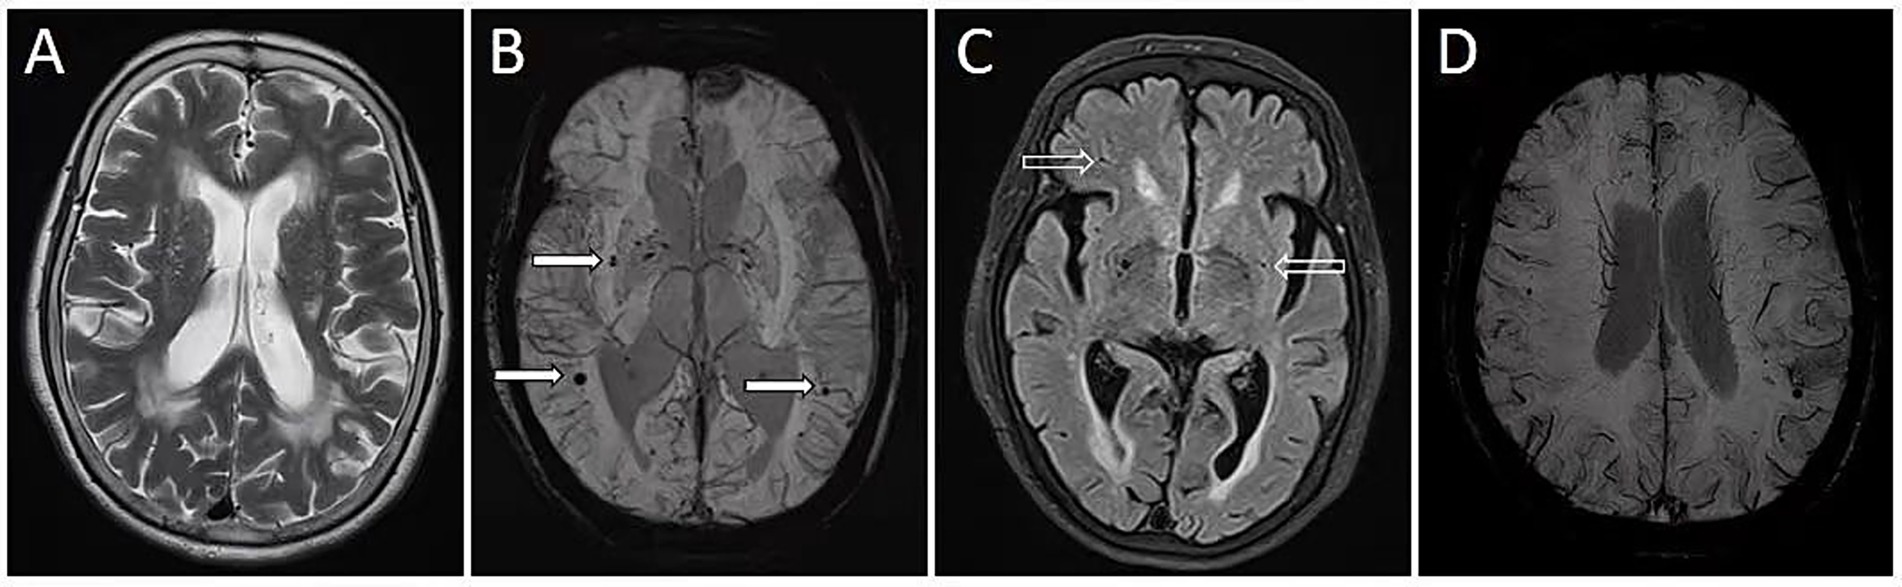

2.5 Measurement of WMH, LI, and CMB

Figure 1. Quantitative neuroimaging markers in a hypertensive patient with cognitive decline. A 71-year-old woman with a history of hypertension was admitted due to cognitive decline. She received a score of 8 on the Montreal Cognitive Assessment. Magnetic resonance imaging (MRI) revealed severe white matter intensities (WMH) (A), cerebral microbleeds (CMB) (B, solid arrows), and lacunar infarctions (LI) (C, hollow arrows). Quantitative analysis using the AccuBrain@ software revealed a WMH volume of 59.7 mL, CMB count of 23, and LI count of 17. MRI susceptibility-weighted imaging also identified discontinuous deep medullary veins (DMV) (D), with a DMV score of 15.